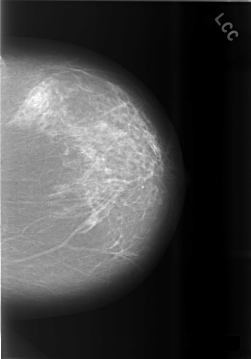

C_0479_1.LEFT_CC

LEFT_CC LINES 5736 PIXELS_PER_LINE 4016 BITS_PER_PIXEL 12 RESOLUTION 50 NON_OVERLAY